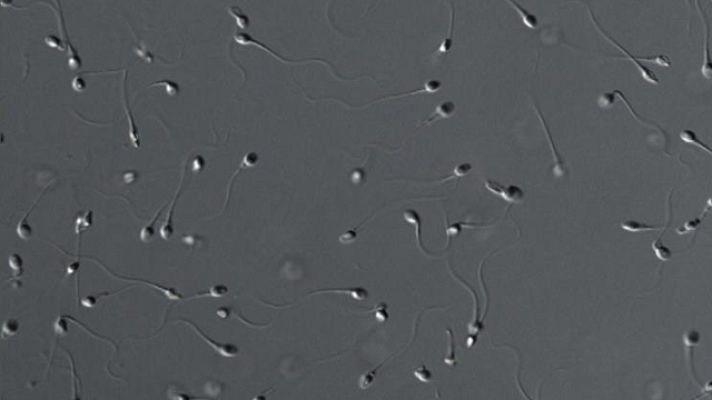

Un estudio del CSIC y el Instituto Marqués de Reproducción Asistida asegura que la mala calidad del semen puede estar relacionada con los tóxicos que los niños reciben de la madre durante el embarazo y la lactancia. La presencia de contaminantes es mayor en zonas más industrializadas.